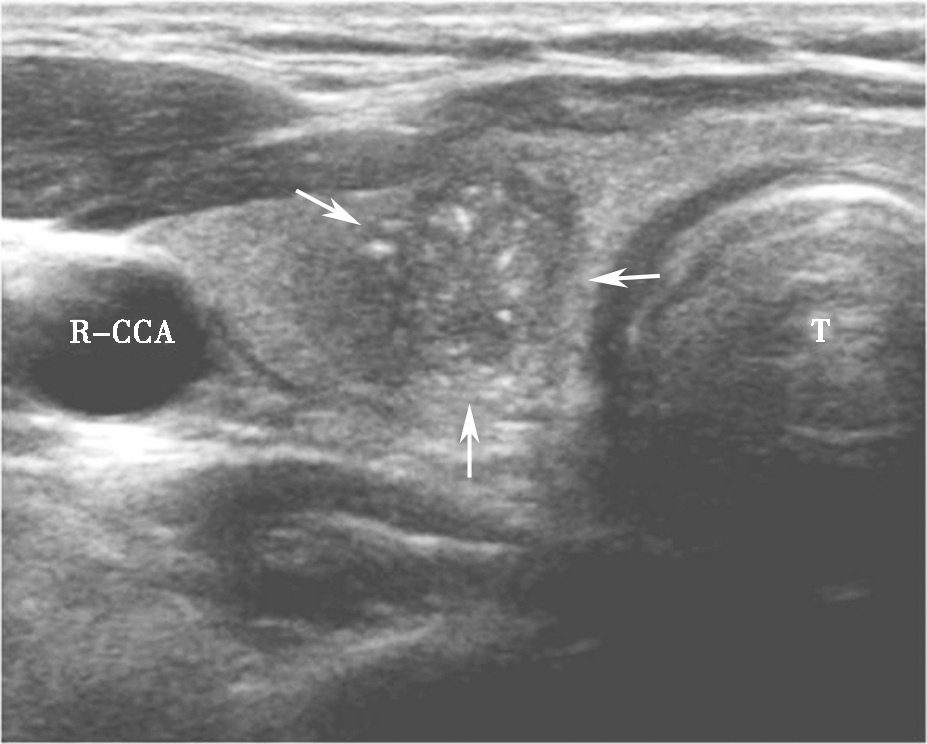

图10颈部正中偏右横切面:甲状腺右叶可见低回声(箭头所示),形态多不规则,边界不清,内可见点状强回声(微小钙化)。T:气管;R-CCA:右侧颈总动脉

,形态多不规则,边界不清,内可见点状强回声(微小钙化)。T:气管;R-CCA:右侧颈总动脉.jpg)